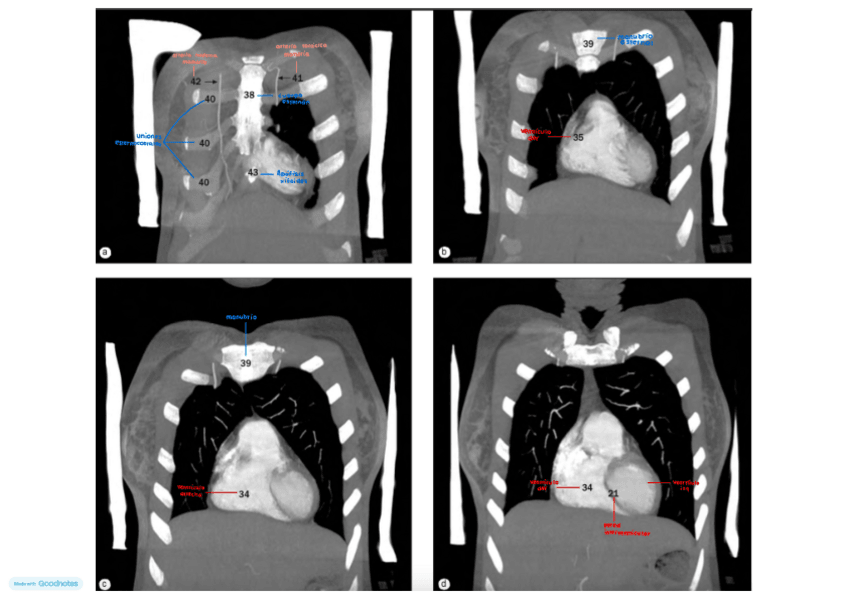

He publicado nuevos apuntes de Técnicas de Tomografía Computarizada y Ecografía: TC Y ECOGRAFÍA

IMAGENES-TORAX-CORONAL-con-antomia.pdf